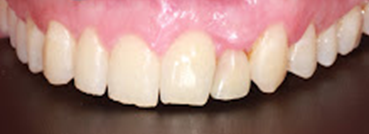

Tras la colocación del implante (Figuras 9 y 10), se rebasó el provisional con resina acrílica autopolimerizable (Bosworth Trim, Bosworth Company) y se cementó mediante un cemento de resina dual (RelyX Unicem 2, 3M Espe, 3M, Saint Paul, Minnesota, USA). Posteriormente, se comprobó la oclusión con papeles de articular de 12 y 8µm con el objetivo de que el provisional no tuviera contactos ni en máxima intercuspidación ni en guía anterior ni guía canina, y no se modificó durante los 4 meses siguientes, aunque sí se revisó al paciente durante el periodo de osteointegración, a las 8 semanas de maduración de los tejidos blandos (Figura 11).

Tras 4 meses de la colocación del implante de circona y la corona provisional (Figura 12), se procedió al escaneado intraoral del muñón para la confección de una corona de circona monolítica.